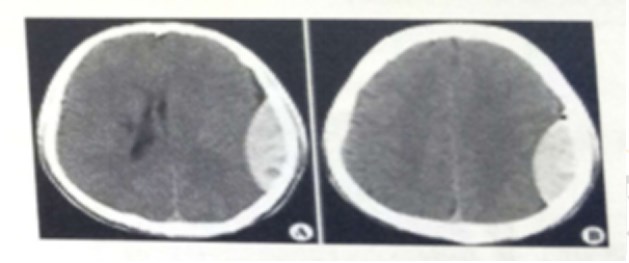

试题:男,44岁。头部外伤12小时。结合CT片,此诊断为(2分)

A.硬膜下血肿

B.脑出血

C.硬膜外血肿

D.颅骨骨折

答案:C